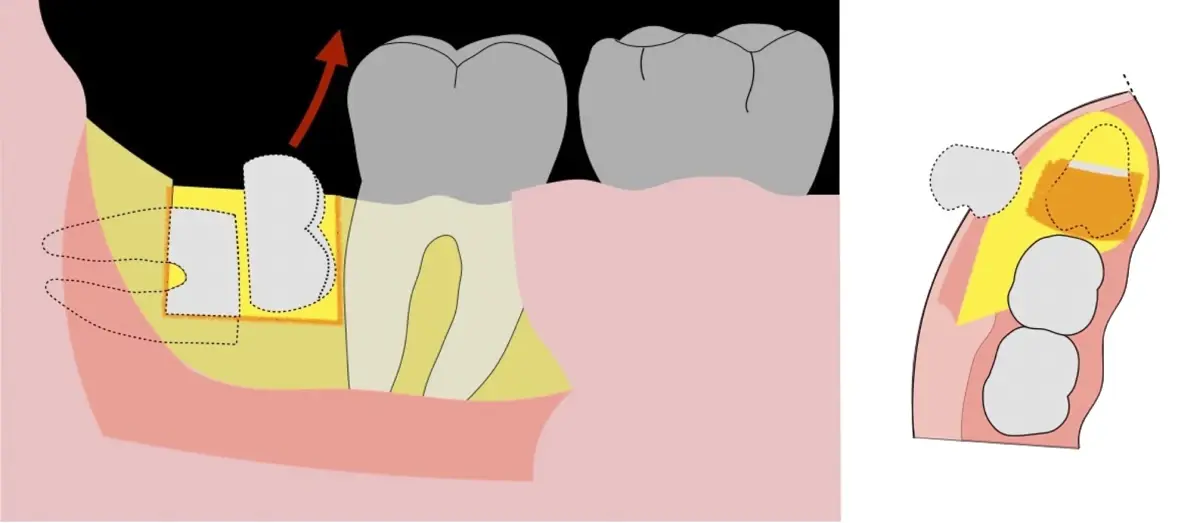

El procedimiento se inicia colocando anestesia troncular para bloqueo del nervio dentario inferior y sus ramas. Luego, se establecerá el diseño de acceso según la disposición de la molar a extraer. Para fines didácticos, se explicará cómo se realizaría la extracción de la molar de la Figura 1: se realiza una incisión horizontal a nivel de la zona retromolar hasta llegar a distal de la segunda molar, continuándose con una incisión intrasurcular hasta mesial de la segunda molar, finalizando con una incisión vertical a espesor total hasta llegar a la línea mucogingival (Figura 2).